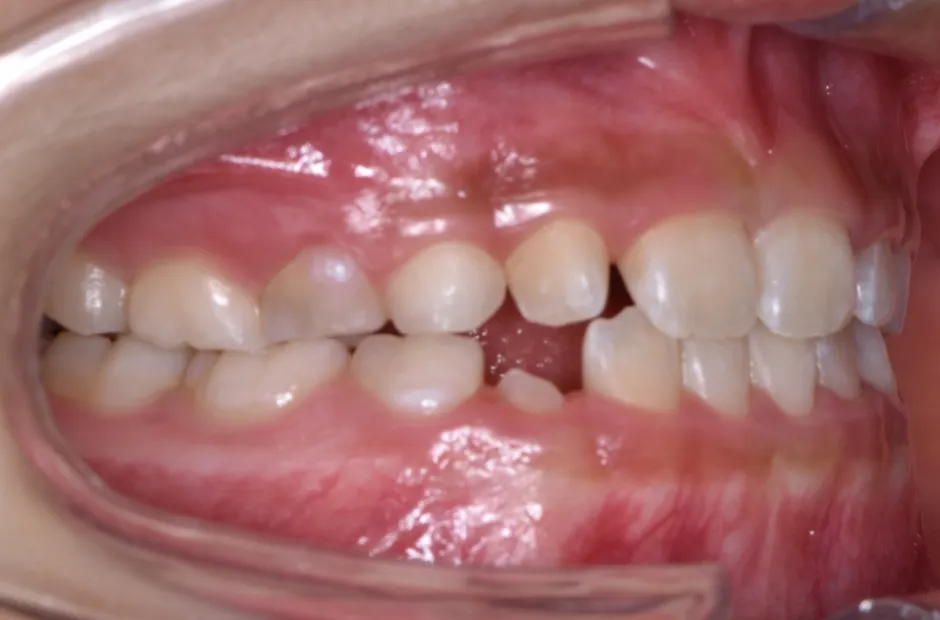

前歯部反対咬合

| 診断名・主訴 | 前歯部反対咬合 |

|---|---|

| 年齢・性別 | 14歳・男性 |

| 治療期間・回数 | 1年2か月 |

| 治療に用いた主な装置 | ブラケット矯正 |

| 抜歯部位 | なし |

| 治療費 | 60万円(税抜) |

| リスク・副作用 | 装置による違和感・疼痛・歯肉退縮・歯根吸収・虫歯のリスクなど |

治療前

治療後